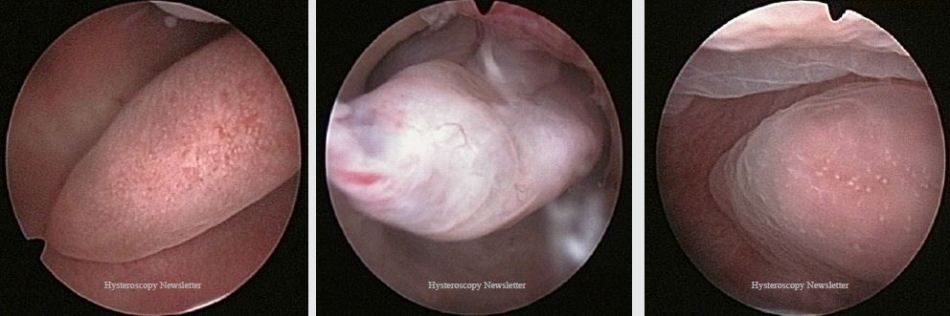

Endometrial polyps originate as focal hyperplasia of the basalis layer of the endometrium and become localized growths of endometrial tissue covered by epithelium containing therein a variable number of glands, stroma and blood vessels. They are usually benign, but 0.5-1% can become malignant.

Polypectomy is indicated for any symptomatic endometrial polyp. Removal of asymptomatic polyps is also frequently recommended, but has not shown a significant benefit.